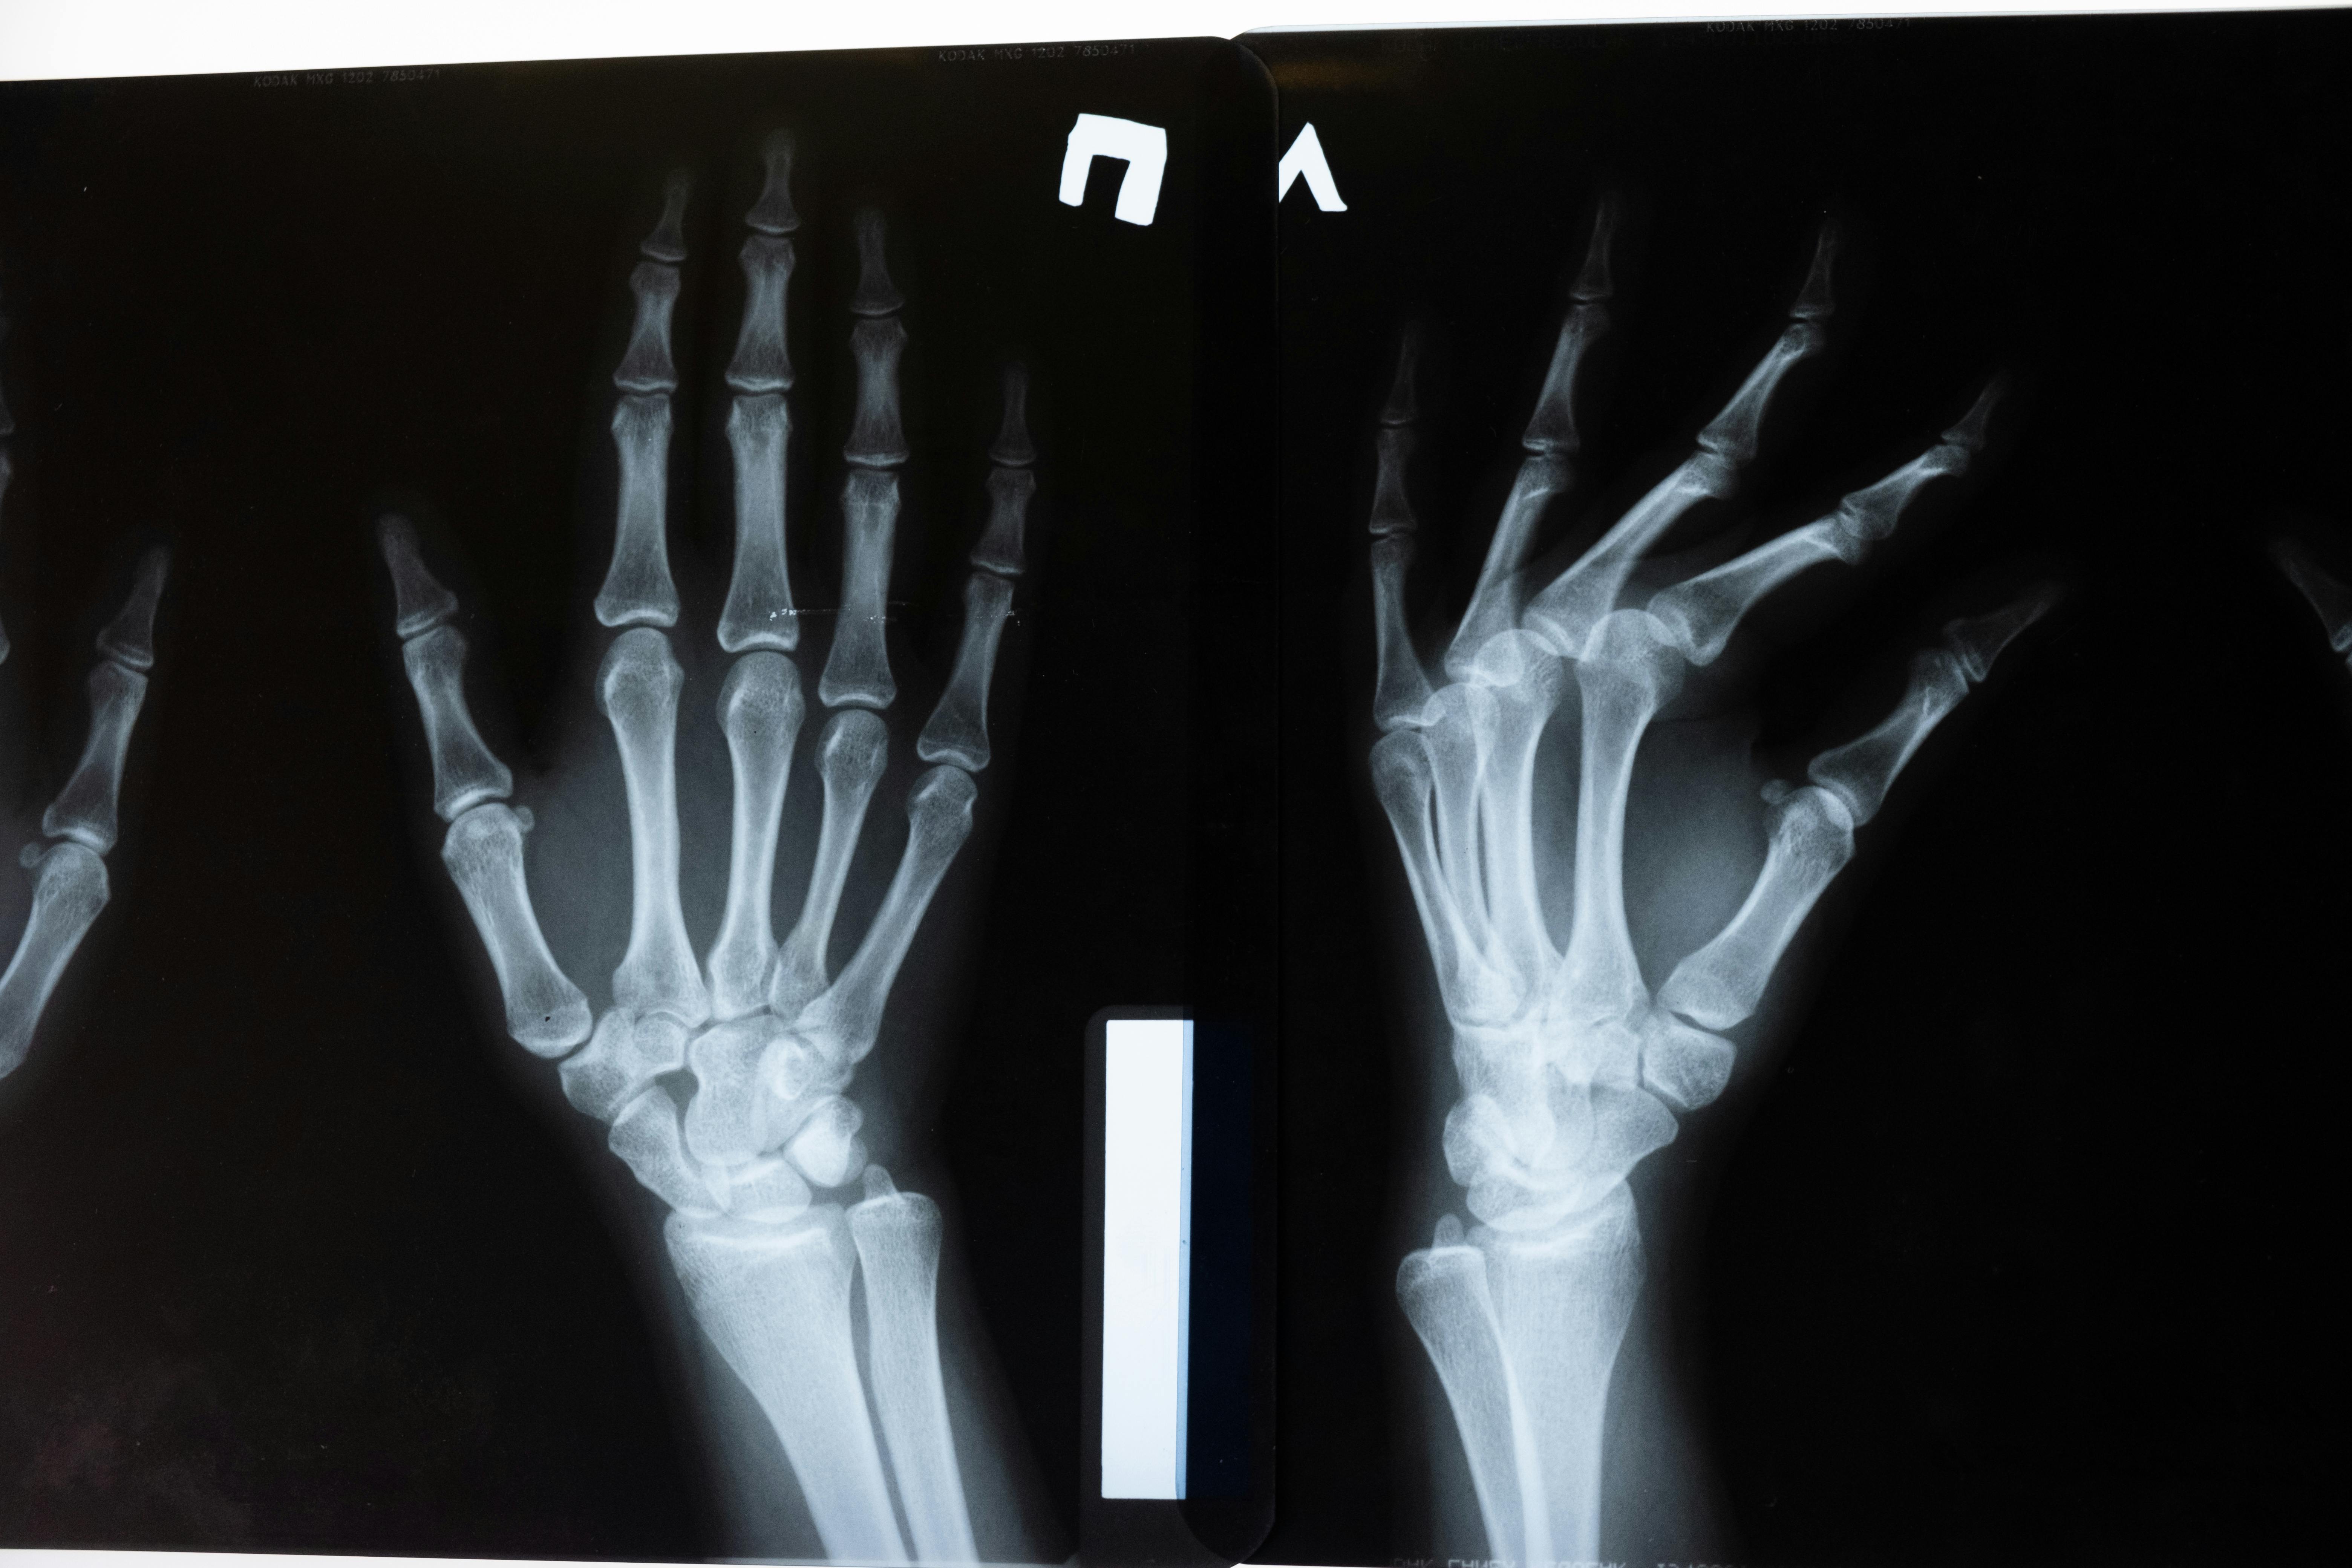

“El médico de primera línea que atiende una fractura debe valorar al paciente y cuando existan factores de riesgo, indicar las pruebas de diagnóstico de osteoporosis, como una densitometría ósea, un examen totalmente indoloro.

En caso de contar con un diagnóstico positivo, debe indicar un tratamiento y así evitar que la persona sufra más fracturas en el futuro”, señaló el doctor Max Saráchaga, director médico de Amgen.

Foto de cottonbro studio: https://www.pexels.com/es-es/foto/anatomia-huesos-examen-rayos-x-5723885/